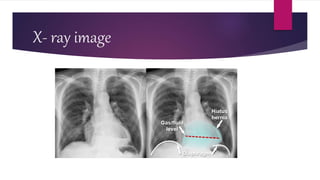

Assessment and diagnostic findings

 Diagnosis is typically confirmed by x-ray studies ;

 Barium swallow ,

 Esophagogastroduodenoscopy (EGD),

 Which is the passage of a fiberoptic tube through the

mouth and throat into the digestive tract for visualization

of the esophagus , stomach ,and small intestine

;esophageal manometry

 Or chest CT scan

X- ray image